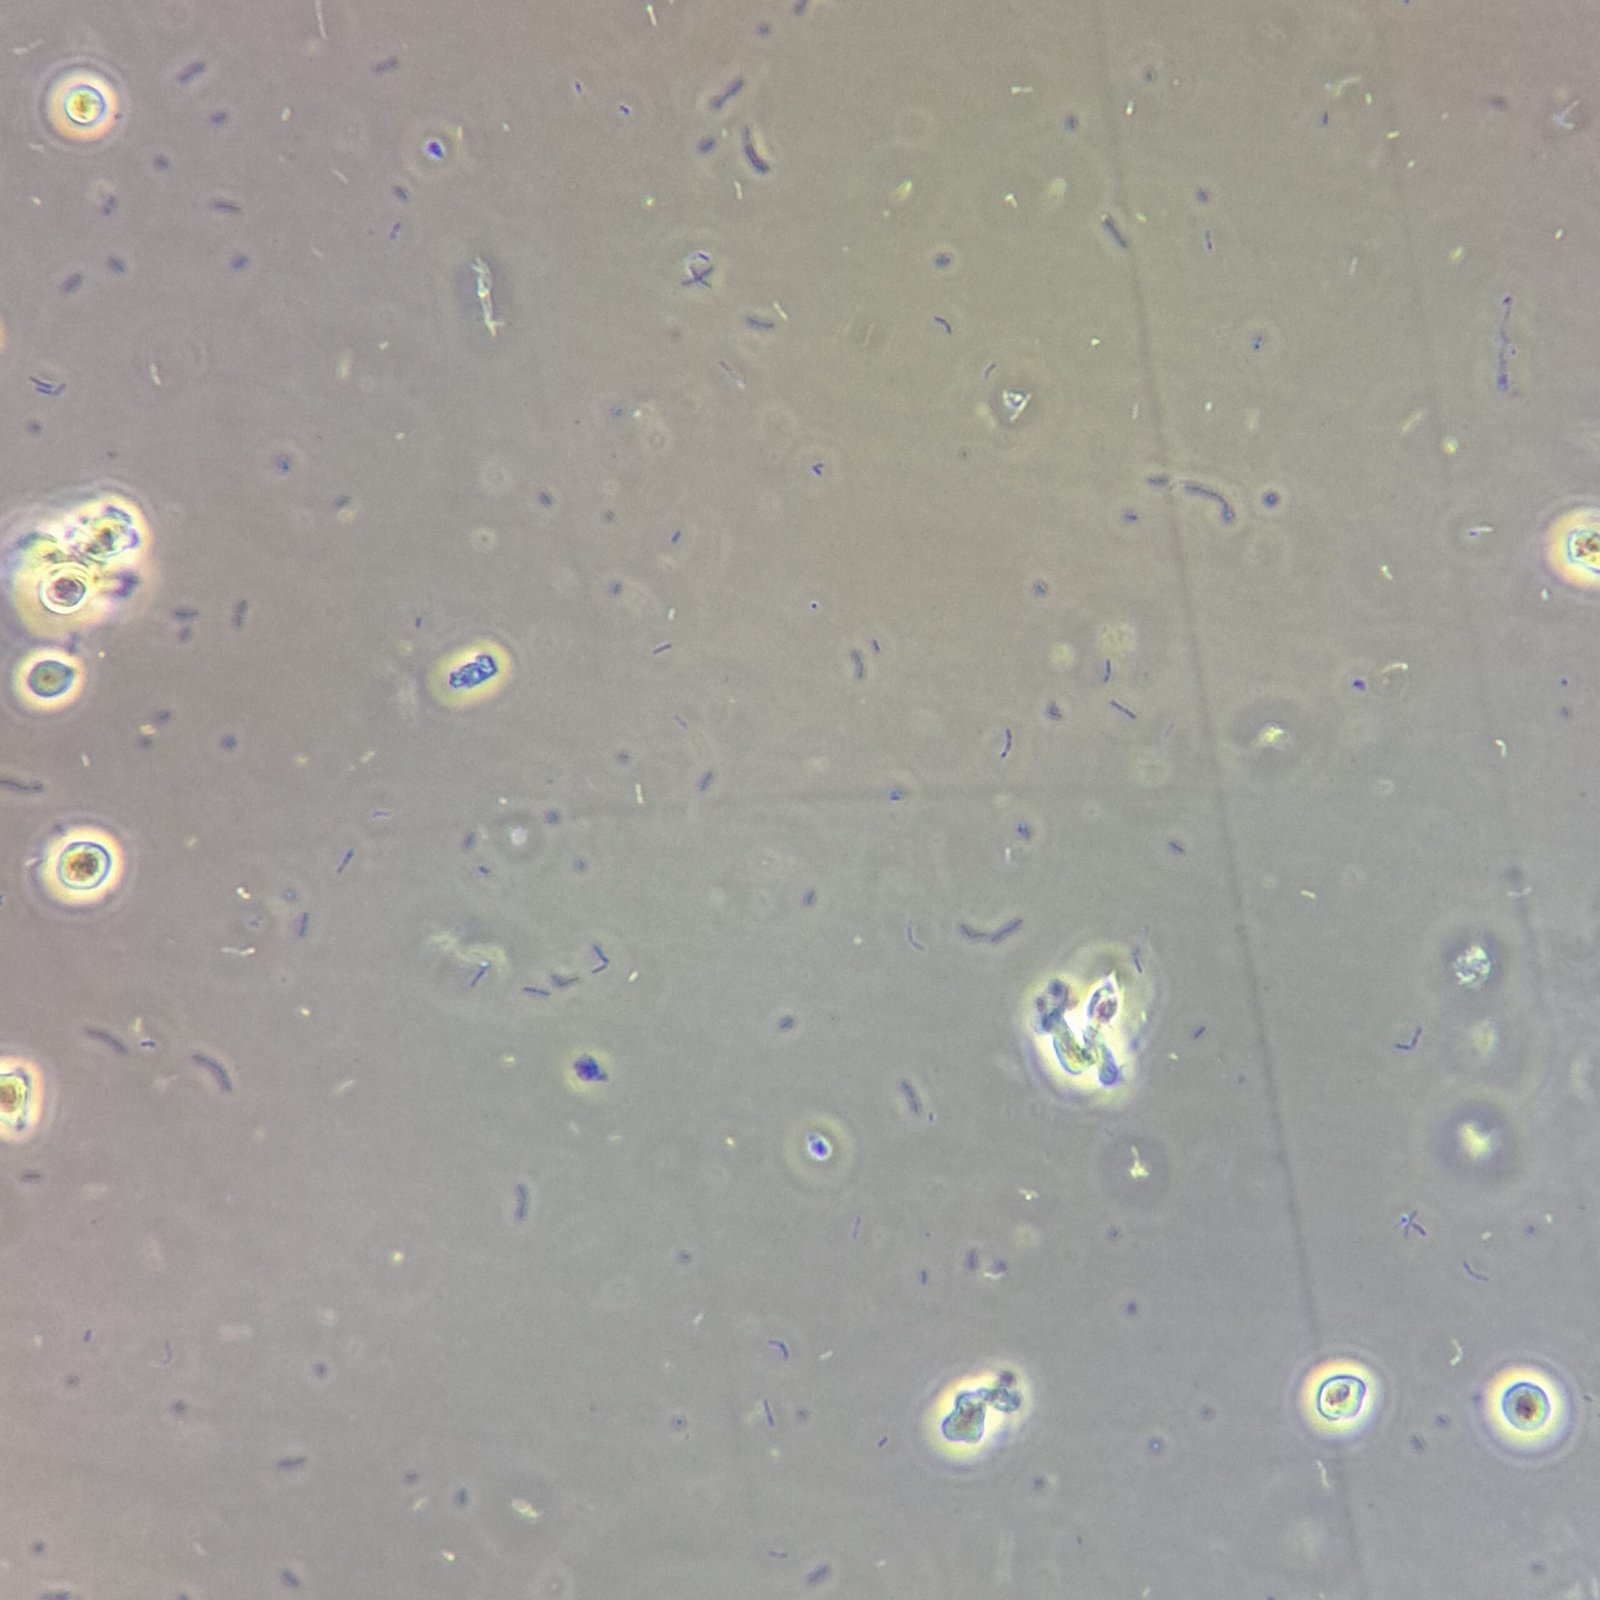

Trichomonas can look like a white blood cell when non-motile which is why motility is usually necessary to positively identify by microscopy.

Gallery